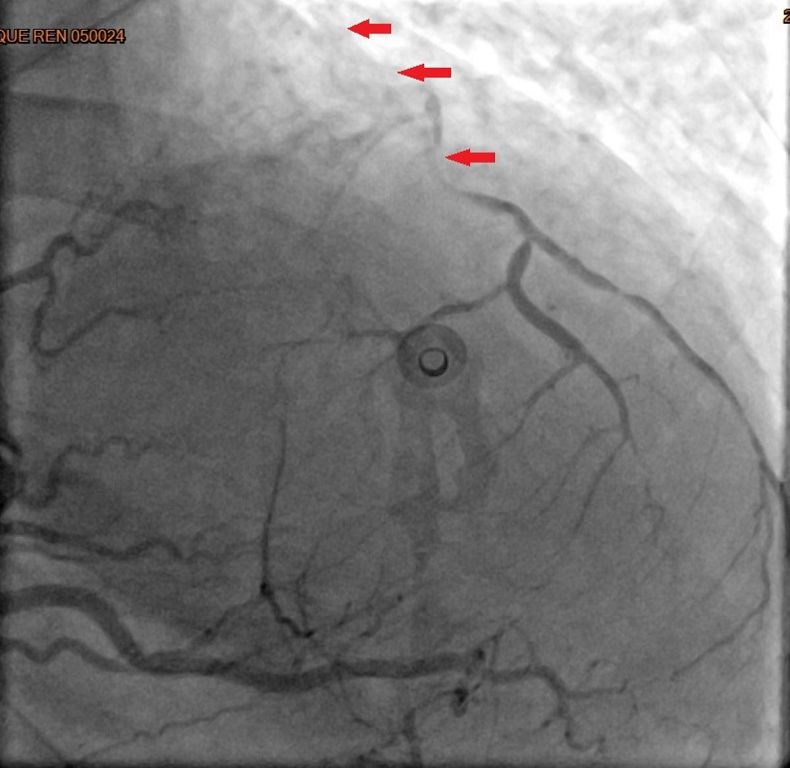

38歲的林小姐平常除了工作以外,最大的興趣是追星,雖有高血脂及心臟病家族史但平時身體無恙,去年冬天前往演唱會途中,於捷運站內突然喪失意識,站內人員立即協助施行CPR,隨後EMT前往接手急救與電擊,並立即送往台北慈濟醫院急診,一連串急救處置後,經心導管檢查確認為急性心肌梗塞。由於三條冠狀動脈均出現嚴重阻塞,其中最主要的左前降支近端更呈現完全阻塞狀,已無法透過氣球擴張或支架方式處理,考慮患者年紀尚輕,心臟血管外科宋鎮宇醫師緊急實施冠狀動脈繞道手術,讓她免於因持續灌流不足引發的惡性心律不整、心臟衰竭等併發症。術後經歷拔管、病房積極的心肺復健,於兩週後返家。後續門診持續藥物治療,並與宋醫師一同討論調整生活作息及運動習慣,病況穩定後順利重回追星生活,但也因此更重視健康的飲食與人生。

「通常需要做到緊急手術的,大多是急性心肌梗塞。」宋醫師說明,緊急心臟手術為了減少缺血休克時間,通常得由正中打開胸骨,快速建立體外循環,進而施行繞道手術。以林小姐為例,醫療團隊當下以主動脈氣球幫浦與強心劑協助穩定血壓,再採取內胸動脈及大隱靜脈完成所有血管的接合,阻塞的左前降支則以內胸動脈供血,讓足夠的血流能夠重新灌注缺氧的心肌,重獲新生。國外統計指出,以此方式接合的血管,十年暢通率可維持達90%。此外,若是穩定型的冠狀動脈心臟病,病人可在與醫師討論評估後以達文西機械手臂輔助的方式以小傷口進行,但此項手術仍然有條件的限制,得考量病人的體型、病灶的位置,且需在資格認證的醫院及醫師指導下進行。